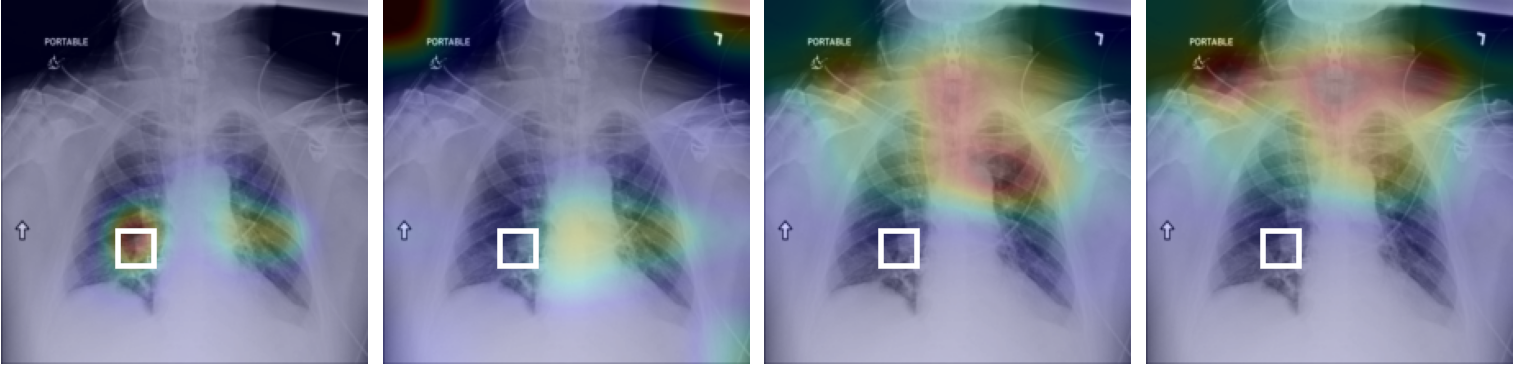

Linear Probing Evaluation: Table 1 presents the experimental results on NIH and SIIM-ACR datasets under linear probing protocol. Specifically, the parameters of encoder remain frozen while that of the linear layer get updated. For NIH, we evaluate the performance by sample labeled subsets from the official train set and report the official test set results in terms of AUC score. Similarly, on MuRed and ODIR datasets, the test set AUC score is reported by evaluating 10% of labeled training data. For pneumothorax segmentation on SIIM-ACR, we report the results in terms of dice score by updating the parameters of the decoder network while that of the encoder remains frozen. Supervised learning (Sup.) notably yields lower AUC scores than the SSL methods. The proposed approach consistently outperforms other baselines across varying degrees of labeled data, specifically for the 1% subset from NIH, the our approach achieves the highest AUC score of 65.1% with an average performance gain of more than 3% from all the baseline methods. Fig 2 presents the diagnostic maps for different pathological conditions, corresponding to the 10% labeled samples from NIH. A similar trend is observed for MuReD and the ODIR dataset, where the proposed approach outperforms the baselines with a considerable average margin of more than 3%. This indicates the method’s ability to extract meaningful representations from unlabeled data for the subsequent downstream training using limited labeled samples. Furthermore, a similar improvement in AUC scores is observed with increased labeled data. The proposed approach also results in the highest dice score of 57.5% on pneumothorax segmentation, with an improvement of 1% compared to the best-performing baseline.